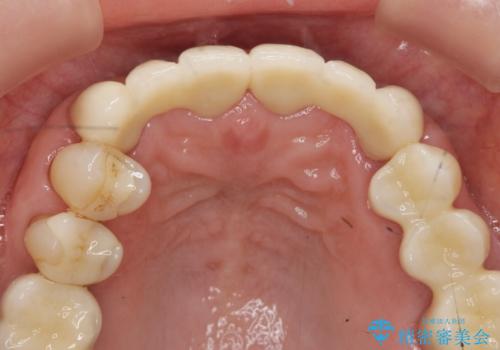

不自然な前歯ブリッジ ジルコニアブリッジによるやり替え

- 20年前に入れたブリッジの見た目の改善を求めて来院されました。

丁寧に現在装着されているブリッジを除去後、精度の高いジルコニアブリッジで審美性の改善を計画します。

- 66万円(仮歯・ジルコニアクラウン×6)費用は治療当時の料金となります

前歯に限らず拡大鏡を用いた精密な形成・シリコンを用いた精度の高い印象を徹底することで治療全体の質を高め、審美性だけでなく長期的な予後を期待することができます。